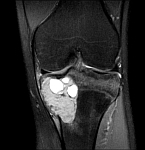

• Tumor surgery of the musculoskeletal system

• Resection of benign and malignant tumors of the bone and soft tissue

• Reconstruction of bone defects by biological procedures (from spongiosaplasty to bone transfer)